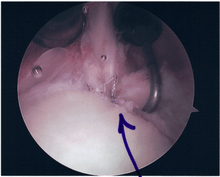

Surgical treatment of SLAP tears has become more common in recent years. The success rate for repairing isolated SLAP tears is reported between 74-94%.[8] While surgery can be performed as a traditional open procedure, an arthroscopic technique[9] is currently favored being less intrusive with low chance of iatrogenic infection.[10]